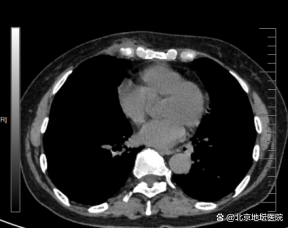

术后影像检查

在胸外科医护团队精心的治疗和照顾下,张阿姨术后恢复顺利,术后第一天就下床活动了,复查胸片提示胸廓重建效果好,肺复张良好。